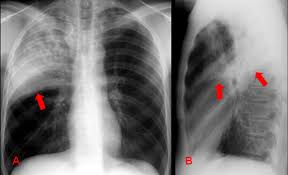

O Pneumotórax consiste em ar na cavidade pleural, acarretando colapso pulmonar parcial ou completo. Na clínica, os...

Atelectasia é o colapso parcial ou total dos alvéolos pulmonares. Quando isso ocorre, a área afetada do...